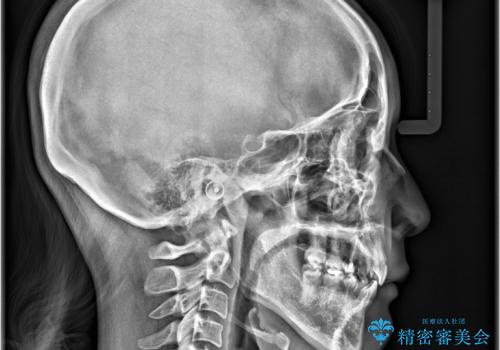

- 「歯のデコボコと前歯が出ているせいで口が閉じにくい」を主訴に来院された患者様です。

上下左右の4番(第一小臼歯)を抜歯をし審美ワイヤー装置で治療を行いました。

抜歯矯正により歯列のデコボコ(叢生)が改善し、前歯の突出も解消されたことで口元が下がり、すっきりとした印象となりました。